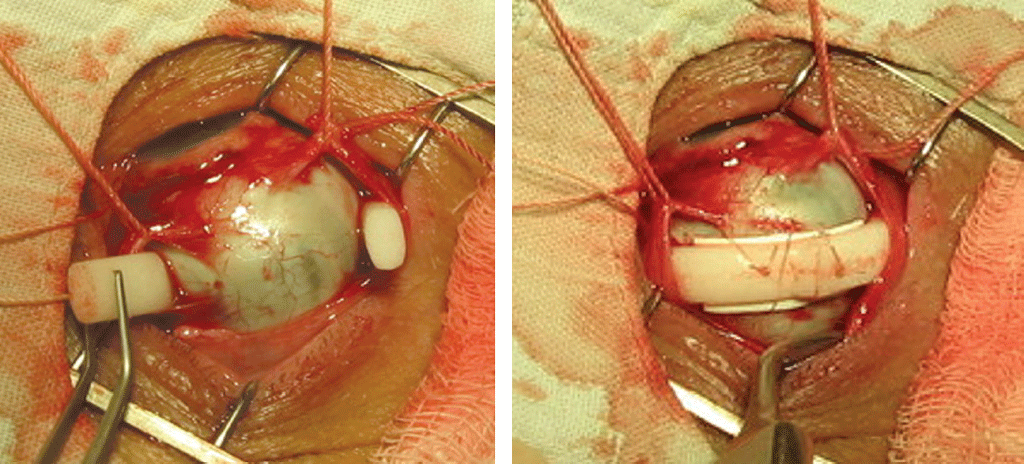

In the period from 2015 to 2016, a total of 1502 surgeries were performed in 1170 patients with primary RRD and its relapse in the Ophthalmology Center of St. Petersburg City Multi-Field Hospital No. 2. Among these patients, extrascleral methods were used for surgery in 466 patients (31%).[8] Extrascleral surgeries were distributed according to their main types. Our practice shows that the most effective and universal procedure is the cerclage, if necessary with the use of focal scleral buckle. (1) Circular scleral buckle (cerclage) was used in 344 surgeries (188 in 2015, and 156 in 2016; 73.8%). For this purpose, as a rule, a tourniquet from a porous silicone sponge was used (see Fig. 2). All patients underwent cryo- or diathermocoagulation of the sclera, if necessary, and puncture of subretinal fluid and introduction of C3F8 gas into the vitreous chamber. (2) Cerclage with a tape + local scleral buckle was used in 93 surgeries (46 in 2015, and 47 in 2016; 20%). The cerclage was performed using a silicone tape 2 mm wide in combination with focal buckle of the tear site with a wide or narrow silicone splint with a channel for the tape or a polytetrafluoroethylene plate of the required thickness (see Fig. 3). We also used plates of this material as “pads” for the cerclage tape or tourniquet at the areas of thinned sclera in order to prevent the development of pressure sores in the future (Fig. 4). (3) Additional scleral buckle was used in 29 surgeries (14 in 2015, and 15 in 2016; 6.2%). It was performed in incomplete retinal reattachment, as a rule, in the next days after the first extrascleral surgery. An additional buckle, usually modeled from polytetrafluoroethylene plates of different thickness and area, was positioned under the previously performed cerclage in order to enhance the sclera depression (see Fig. 3).

Fig. 4. Patient S., 68 years old. OS. Pseudophakia. Regmatogenous retinal detachment with multiple tears, a combination of plastic of thinned scleral areas with a polytetrafluoroethylene plate and circular buckling with a silicone tourniquet

Рис. 4. Пациент С., 68 лет. OS. Артифакия, регматогенная отслойка сетчатки с множественными разрывами. Сочетание пластики истончённых участков склеры пластинкой из политетрафторэтилена и кругового пломбирования силиконовым жгутом. Вырезанная несколько шире пластинка уложена под жгут во избежание пролежня, наложены Х-образные швы. После операции сетчатка прилегла

This measure is effective in cases of insufficient blocking of retinal tear in the early postoperative period, detection of a tear that was not diagnosed at the preoperative stage, and to weaken traction forces. For additional retinal fixation, transpupillary laser coagulation was performed, if necessary, in the areas of tears or along the depression bank.